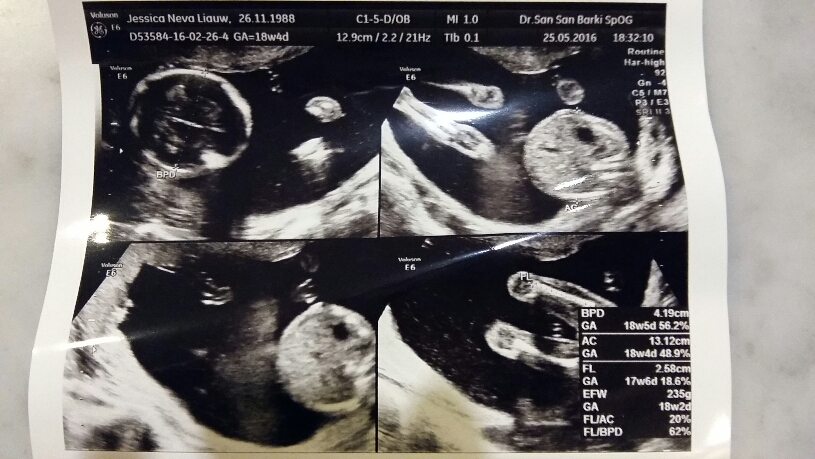

Then I opened my blog, looking for this particular post about when I first felt Nathan living inside me. That was during week 19 and there were pictures from the USG dated 7 March 2014 and Nathan was 18w4d. I realized that my appointment was rescheduled to when baby no. 2 is exactly 18w4d. Coincidence? I think it’s destined to be.

Today we went for our appointment, meeting our baby no. 2 who’s growing healthy and well. At this stage, baby no. 2 is slightly lighter than N. Our obgyn said that he’s 70% sure of the gender. I actually think that he’s 100% sure but to avoid disappointment, he told us to wait for another month. Oh well…